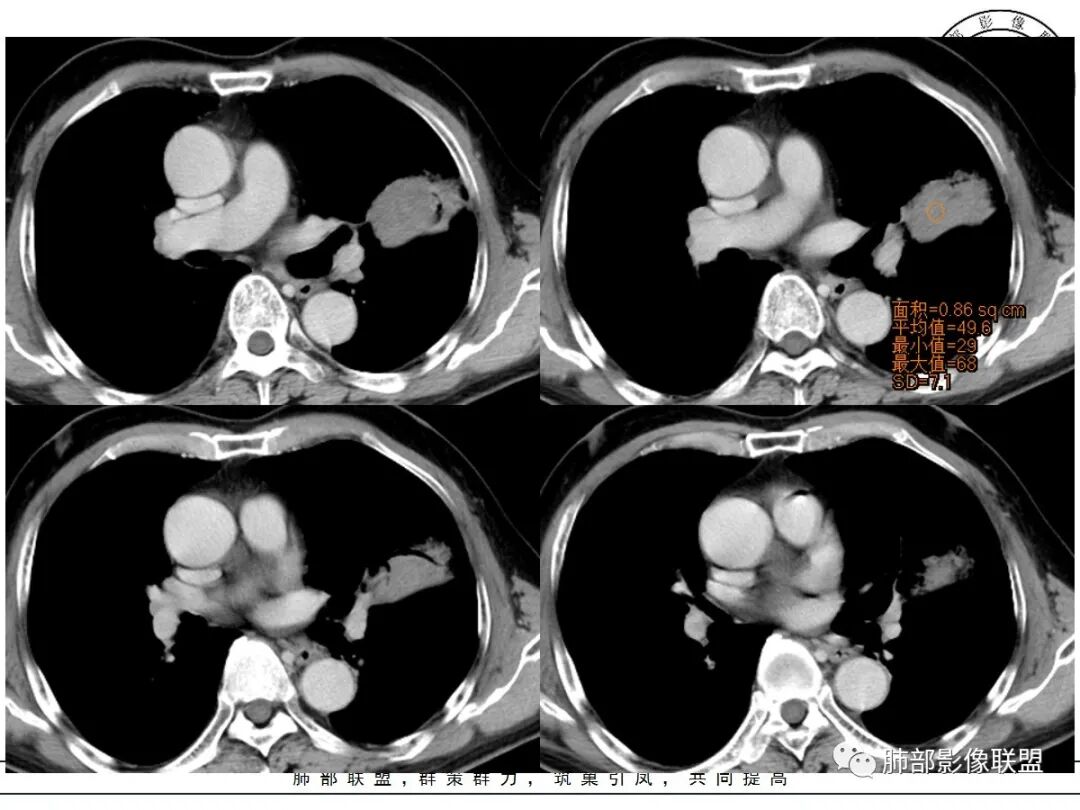

左肺上叶类圆形软组织影,边界较清楚,其内密度均匀,外侧缘可见空气新月征,并可见点状钙化,增强扫描可见均匀强化,病灶周围可见磨玻璃渗出性密度影,斜裂侧光滑平整。考虑炎性病灶,以肉芽肿性炎症为主(如真菌性肉芽肿),鉴别结核(无卫星灶,无多态性),肺癌(无毛刺,分叶等恶性征象,)细菌性炎症(密度一般不这么致密,很少钙化及空气新月征)。

左肺上叶类圆形软组织影,界清,内见空洞影,病灶周围斑片影,可见空气支气管征,未垮叶。考虑炎性病变,糖尿病四大金刚,肺克?毛霉?

老年男性,血糖升高六年,反复咳痰咳嗽3周,左肺上叶近斜裂类圆形肿块影,边缘伴磨玻璃影,边界不清。内部可见支气管走行、钙化、小空洞,叶间裂局部膨隆,增强扫描轻度强化,内部可见小的低密度区,边界尚清。考虑为炎性病变可能性大。

左肺叶裂旁实变影,宽基底与叶裂胸膜相连,边缘平直,部分略膨隆,病灶近段及上段支气管深入病灶内,部分壁略增厚,远端支气管截断,似有小空泡,壁规则,内部可见高密度钙化,周围可见模糊的GGO,血象正常,考虑结核(NTM),鉴别隐球菌,奴卡,放线菌。

老年男性,66,反复咳嗽、咳痰3月。糖尿病,血象不高。

胸部CT:左肺上叶类圆形肿块影,边界较清楚,密度较均匀,内可见小片坏死、偏心空洞、空气新月征、点状钙化,周围晕、絮状渗出、边缘模糊,支气管扩张、充气征、支气管进入病灶堵塞,叶裂牵拉明显,增强扫描中度均匀强化,纵隔可见淋巴结。考虑:炎性病灶,肉芽肿性炎症,曲霉?毛霉?鉴别:TB,淋巴瘤。

左上肺类圆形肿块影,边界较清楚,支气管通畅略扩张,周围磨玻璃影,其内密度均匀,外侧见空气新月征,且见点状钙化。叶间裂光滑稍膨隆。老年男性,糖尿病,高血压,痰培养克雷伯菌。综合考虑炎性病灶,克雷伯合并真菌感染,曲霉。结核合并真菌。鉴别肺癌合并感染。

左肺上叶类圆形软组织影,边界稍模糊,其内密度均匀,外侧缘可见空气新月征,并可见点状钙化,增强扫描渐进性强化,病灶周围可见磨玻璃影,斜裂侧光滑平整,气管未见明显闭塞,淋巴结未见肿大,糖尿病患者,首先考虑感染性变,结核并曲霉?